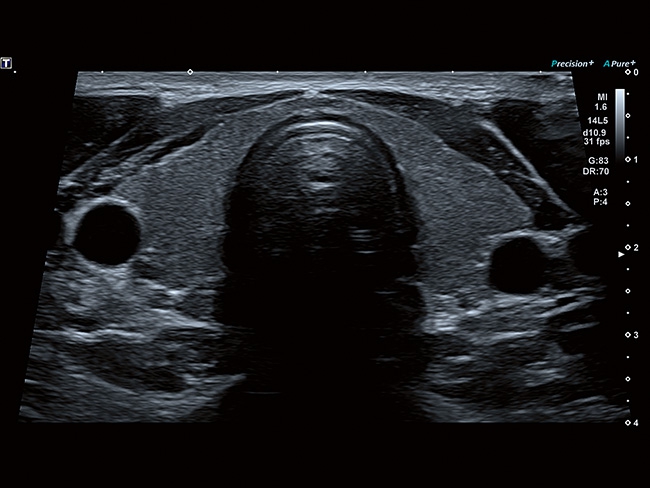

Aplio a550 – это многофункциональная УЗИ система экспертного класса. Высокое качество изображения и интуитивно понятный интерфейс поможет вам обеспечить высокую производительность и скорость проведения исследования. Совершенные технологии визуализации помогают повысить диагностическую уверенность даже в сложных случаях.

Стационарная цифровая ультразвуковая система Toshiba (Canon) a550. Современные технологии визуализации, цифровое формирование луча, удобная для работы панель. Характеристики, удовлетворяющие требованиям к системам УЗИ экспертного класса.

Система имеет компактные размеры, удобную центральную педаль блокировки, высококонтрастный экран в диагональю 23", регулировка по высоте на расстояние более 36 см, а панель управления и монитор могут быть настроены для любого положения сканирования.

Отличная цветопередача с высокой детализацией и четкостью изображения. Устройство подходит для профессионального использования в частных кабинетах и крупных медицинских центрах. Комплектация сканера применима для самых разных исследований. Широкий диапазон прикладного клинического программного обеспечения высокоэффективен для общих исследований, сердечно-сосудистых, гинекологических, ортопедических, урологических.